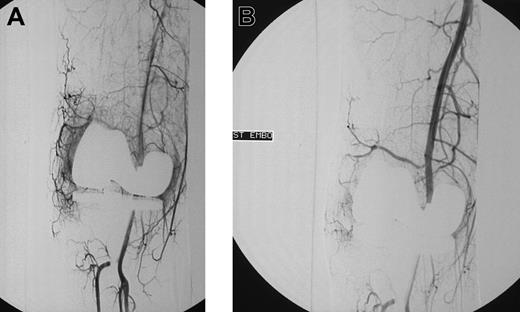

Initial angiograms demonstrated a blush, indicative for hyperemic tissue as cause of bleeding in 15 patients (Figure 1A-B); in 2 patients a false aneurysm was observed (Figure 2A-B); in one patient a true aneurysm was observed; and in 3 patients an arteriovenous shunt in combination with an aneurysm was observed. In all these cases embolization of the feeding arteries was performed. However, in some cases, it was not possible to embolize all the bleeding arteries. In 2 patients, the cause of bleeding could not be localized (one patients with postoperative knee bleeding and one with spontaneous elbow bleeding) and embolization was not performed.

Blush in a patient with knee bleeding. Angiogram shows blush in a patient with recurrent massive knee bleeding following joint replacement before (A) and after (B) embolization.